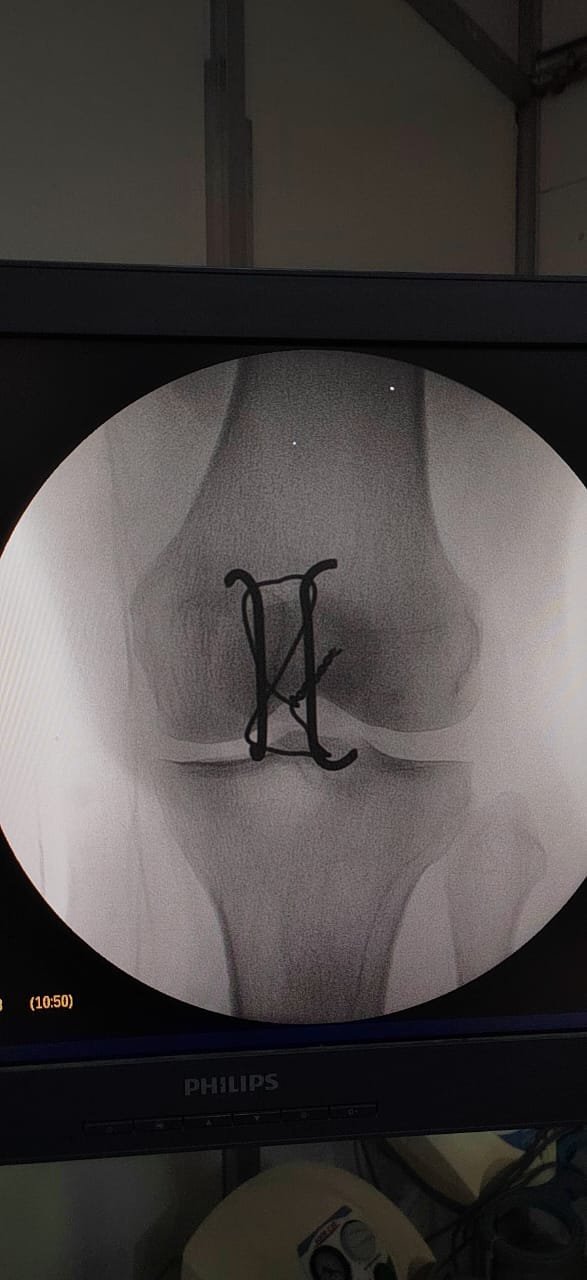

تركيب كويرات بالرضفة اليسرى لمريض.

وقد تمت العمليتان بدقة عالية وباستخدام أحدث التقنيات، وشارك فيهما فريق طبي وتمريضي وفني متكامل ضم:

الأطباء: د. شريف البيومي توفيق (عظام)، د. عيد السيد حسن (عظام)، د. ماهر فوزي كامل (تخدير).